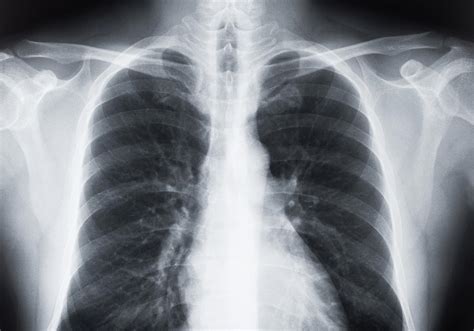

Receiving medical imaging results can often feel overwhelming, especially when terms like lung scarring on CT scan appear on your radiology report. Finding evidence of scarring—medically referred to as pulmonary fibrosis or interstitial lung abnormalities—can trigger anxiety, but it is important to remember that these findings are descriptive and require clinical context to be fully understood. A CT scan is a highly sensitive diagnostic tool that provides a detailed cross-sectional view of the lungs, allowing doctors to identify changes in the lung tissue that might not be visible on a standard chest X-ray. Understanding what this scarring means, why it happens, and what steps you should take next is the first step toward managing your respiratory health effectively.

When a radiologist identifies lung scarring on CT scan, they are typically referring to the presence of fibrotic tissue. In a healthy lung, the tissue is delicate, thin, and elastic, allowing it to expand and contract effortlessly with every breath. When injury occurs, the body attempts to repair the tissue; however, in certain conditions, this repair process goes awry, leading to the buildup of excess connective tissue.

This scarred or thickened tissue is less flexible than healthy lung tissue. Over time, as this scarring accumulates, it can make the lungs stiff, making it more difficult for oxygen to pass from the air sacs (alveoli) into the bloodstream. This physiological change is what leads to symptoms such as shortness of breath and a persistent, dry cough.